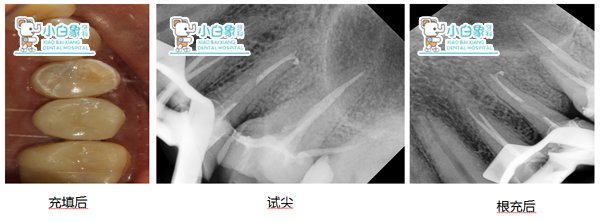

检查:24远中邻合面龋坏达牙本质深层,叩诊(土),温度试验迟钝,牙龈无红肿。25 26全瓷冠修复,边缘密合,牙龈无红肿。全口牙龈部分退缩,牙龈无红肿。

X线:24低密度影近髓角

25 26根充良好

治疗:24必兰麻醉下上橡皮障,去腐质,开髓揭顶,预备根管两根,根长21mm,次氯酸钠冲洗,隔湿干燥 ,试尖,根充,磷酸锌垫底,3MZ250充填,调合。